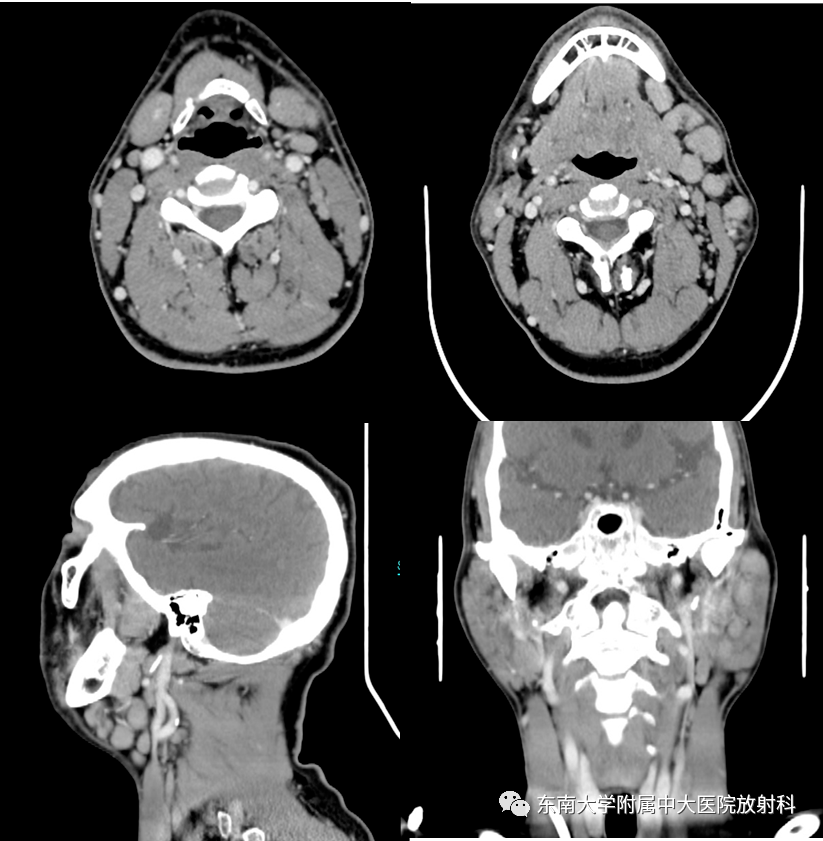

- 全身にできるが特に頭頚部(とうけいぶ;首以上の部分)が多く、その中でも耳下腺またはその周囲に発生することが多い。稀に上咽頭(のど)や口腔内の粘膜下にも発生する。

- MRI検査,CTなどの画像検査